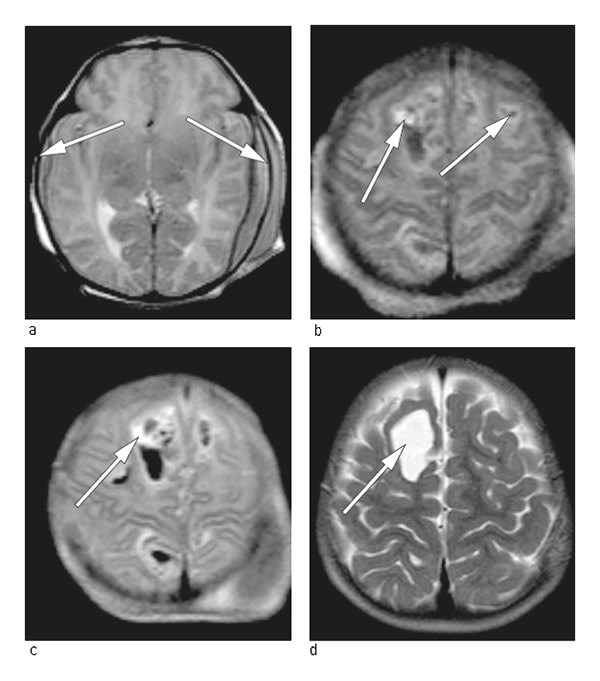

Two healthy, unrelated adults had their first baby after an uncomplicated pregnancy. The birth occurred at gestational age 39 weeks and two days. The child was delivered by acute caesarean section because of occiput posterior, protracted delivery and weak contractions. The baby was limp and pale at birth, weighed 2 740 g and had Apgar scores of 2, 6 and 7 after one, five and ten minutes, respectively. Because of respiratory problems she was ventilated with mask and bag for the first three minutes, then with Neopuff (mask CPAP) for 15 minutes. Multiple petechiae and haematomas on the head were observed immediately after birth. Haematological tests revealed severe thrombocytopenia – 9 · 109 cells/L (145 – 390 · 10⁹ cells/L). Irradiated platelet concentrate from four random donors (15 ml/kg), intravenous injection of 0.8 g/kg immunoglobulin (IVIg) and orally vitamin K were administered. Cerebral ultrasound revealed parenchymal haemorrhage medially in the parietal cortex bilaterally. Closer examination in the form of an MRI of the head revealed bilateral cortical and epidural haemorrhages (Fig. 1). These were interpreted as being fresh. The neurosurgeon recommended further observation and conservative treatment.

Figure 1  MRI of head, T2 image with 1.5 Tesla scanner. The images during the first day of life show a) fresh subdural…

Figure 1 MRI of head, T2 image with 1.5 Tesla scanner. The images during the first day of life show a) fresh subdural haematomas (arrows) and b) mixture of fresh and 3 – 4 day-old intracerebral haematomas (arrows). c) Control after 24 hours shows an increase in the size of one intracerebral haematoma (arrow). d) After 15 months a cavity remains frontally after the largest intracerebral haematoma (arrow)

After discharge the child was monitored by means of blood tests, first monthly and then every second month for six months. The platelet count remained consistently within the normal range (326 – 402 · 10⁹ cells/L). A cerebral MRI was repeated at the ages of one and 15 months (Fig. 1). The child has later shown normal psychomotoric development and is now a healthy five year-old.

The birth of the first child up until surgical delivery took place was protracted. The intracranial haemorrhage was fresh at the time of birth (Fig. 1). One may wonder whether this could have been avoided if the maternal platelet type and antibody level during pregnancy had been known, and a caesarean section had been performed 2 – 3 weeks before term, with compatible platelets available for the child.